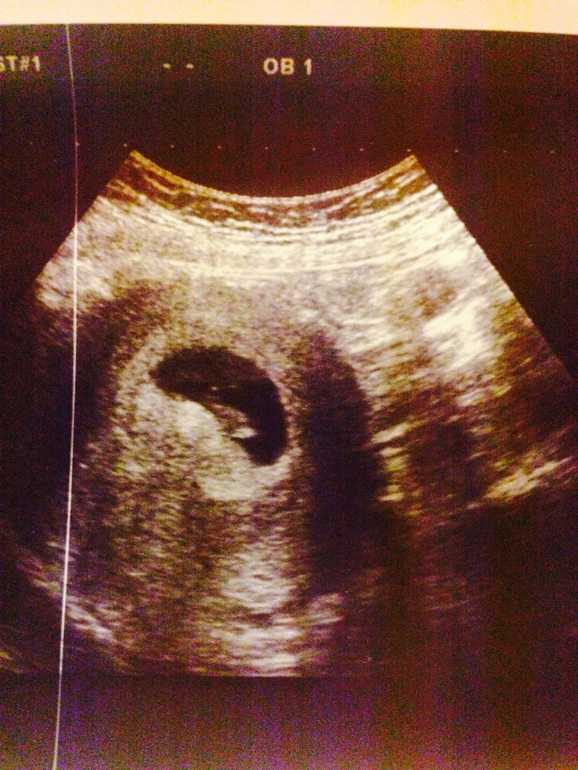

Сегодня стала на учет). Сдала политра крови (520 грн), заполнила кучу бумаг и сделала узи (для собственного успокоения). Была у Паненко. Он посмотрел осень быстро, но сказал все, что необходимо и распечатал фотку. Бусинка уже 13 мм))))

Правда, это удовольствие обошлось в 300!!! грн. Недешево(((. Зато я спокойна - все в норме, соответствует сроку и нормотонус)